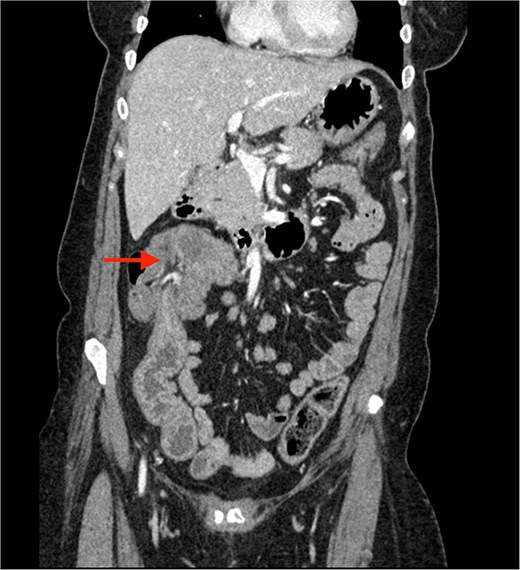

A CECT scan of the abdomen and pelvis revealed circumferential heterogeneously enhancing mucosal wall thickening involving caecum and ascending colon with pericolic fat stranding and ileocolic intussusception along with multiple enlarged heterogeneously enhancing necrotic lymph nodes in right iliac fossa and pericolic region (Figs 1 and 2).

Contrast enhanced CT of the abdomen showing bull’s eye sign (arrow) suggestive of ileocolic intussusception.